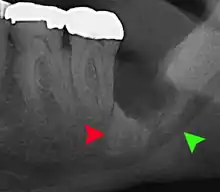

Coronectomy

Coronectomy is a procedure where the crown of the impacted wisdom tooth is removed, but the roots are intentionally left in place. It is indicated when there is no disease of the dental pulp or infection around the crown of the tooth, and there is a high risk of inferior alveolar nerve injury.[31]

Coronectomy, while lessening the immediate risk to the inferior alveolar nerve function has its own complication rates and can result in repeated surgeries. Between 2.3% and 38.3% of roots loosen during the procedure and need to be removed and up to 4.9% of cases require reoperation due to persistent pain, root exposure or persistent infection. The roots have also been reported to migrate in 13.2% to 85.9% of cases.[31]